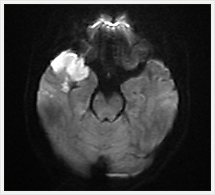

脳血管障害

脳梗塞急性期においてこれまでT2強調画像やFLAIAを撮影しても、梗塞巣を検出できるまでには長時間かかっていましたが、拡散強調画像(DWI:Diffusion Weighted Imaging)では発症後1~2時間で梗塞巣を検出でき、非造影パーフュージョンでは発症直後から虚血巣を描出できるため、より早期脳梗塞診断が行えるようになりました。